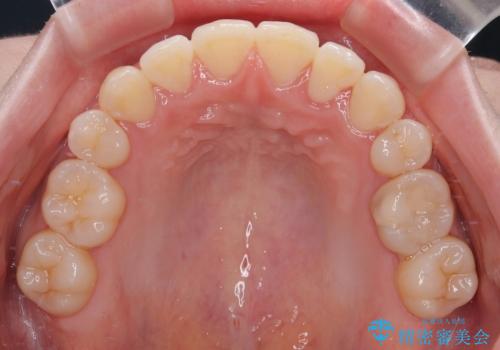

補助装置を併用したおかげで、出っ歯になることなくスムーズに治療を終えることができました。

- 八重歯が気になるとのことで来院された患者様です。

上顎前歯部はデコボコが強く、歯を並べるためのスペースが不足しているため、左右の第一小臼歯を抜歯することとしました。